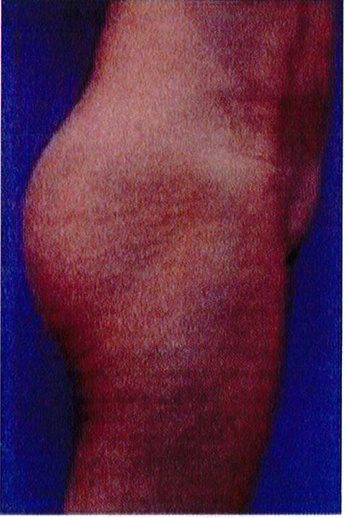

Hình. 18.. (A) Hình anh trước và (B) và sau phẫu thuật làm đầy mông của bệnh nhân được đặt khối implant dưới cân thể tích 225 mL, hai bên.

Bệnh nhân 31 tuổi tiền sử khỏe mạnh, có chỉ định nâng mông bằng implant do thiếu hụt thể tích. Hai khối anatomic implant 225 mL polyurethane dạng gel được đặt ở vị trí dưới cân. Sau phẫu thuật không ghi nhận biến chứng trong suốt quá trình hồi phục, vết mổ liền tốt (Hình 18).

Bệnh nhân 52 tuổi xuất hiện chùng da vùng mông (mức độ nặng), mong muốn giải quyết vấn đề này đồng thời tăng kích thước vòng ba. Hai khối anatomic implant

Hình. 19. . (A) Hình anh trước và (B) và sau phẫu thuật làm đầy mông của bệnh nhân chùng da vùng mông tương đối nhiều. Bệnh nhân được đặt khối implant dưới cân thể tích 330 mL ở hai bên.